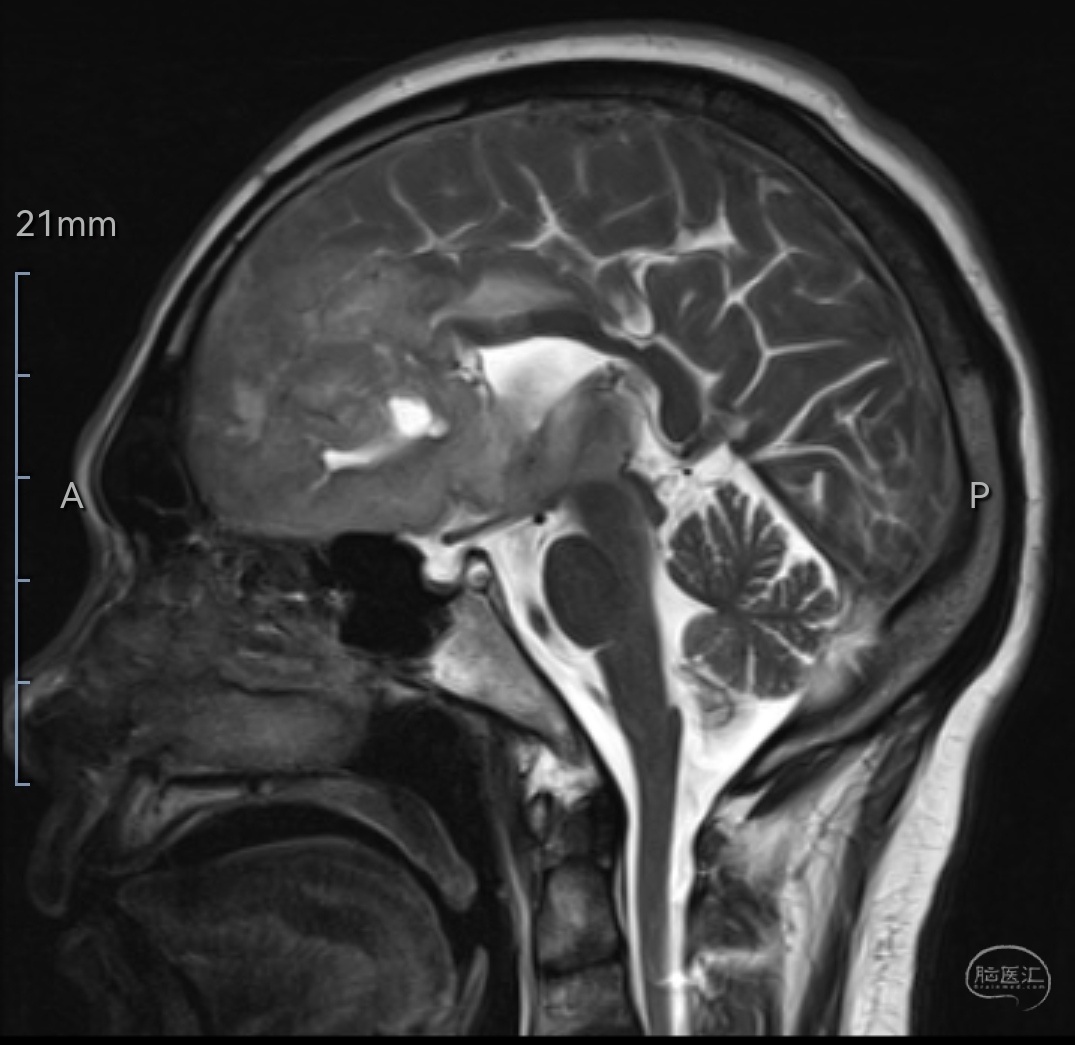

MRIT2相矢状位示肿瘤位于双侧额叶,左侧为主,已侵犯至胼胝体嘴、膝部